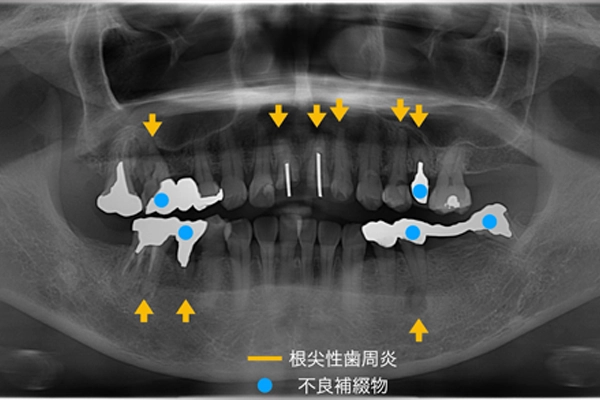

レントゲン写真

下顎頭の変形はなく、顎関節の異常はなく、筋触診でも硬直や圧痛などはありませんでした。

黄色矢印が根尖性歯周炎、青丸が不良補綴物(過去に行った被せ物や詰め物が劣化している状態)がある箇所を示しております。